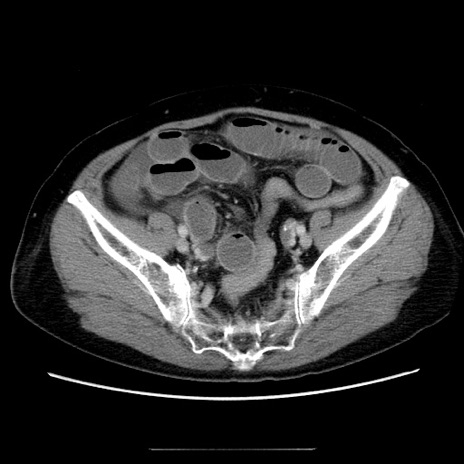

症例5(横断像)

【症例】70歳代女性

【主訴】お腹が張る

【現病歴】1週間くらい前から腹部膨満の自覚あり。昨日夜から増悪したため、本日救急外来受診。

【身体所見】意識清明、BT 36.5℃、BP 165/106mmHg、HR 80bpm、SpO2 98%、腹部:膨満、軟、自発痛・圧痛なし、触診にて不快感あり、腸蠕動音:減弱

【データ】WBC 12600、CRP 1.04